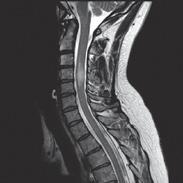

A year ago, Gabriela was walking down a flight of stairs when she lost her balance. Falling head over heels she lay there at the bottom, startled, a little dazed but in a lot of pain, mostly in her lower back. The pain persisted over the course of months with fluctuating severity. About a month ago, she began to experience pain and burning down her right leg into her calf with numbness in the foot. That is what prompted her to come in and see us here in the free clinic where we were providing care in January 2023. We were a team: translators, triage and support staff, and clinicians; two physicians, a physical therapist and myself, providing care for those without insurance in Antigua, Guatemala.

Gabriela was in obvious pain and her exam revealed positive nerve root tension tests and neurological deficits in the right lower leg which resulted in a diagnosis of an S1 nerve impingement likely due to a disc protrusion. I was somewhat concerned, because I was only here for a week and she did not have insurance that would cover surgery if that became necessary. All I could do, I thought, was the best that I could with the time that I had. With that, I treated her daily for the last three days I was there.